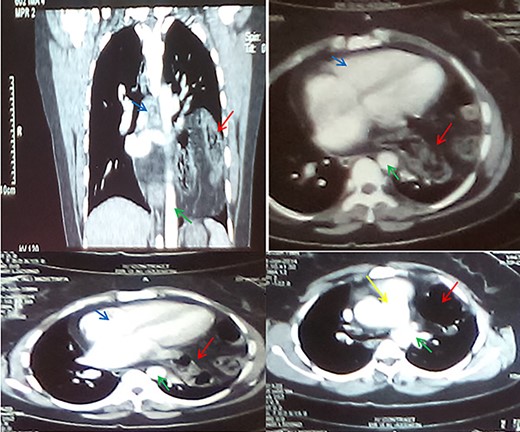

A 35-year-old primigravida female patient complained of mild chest and epigastric pain. Twenty months earlier, she underwent a successful emergent caesarian surgery for preeclampsia, which was performed without complication. Since then, the patient complained of an episodic spasmo-colic pain in the left chest and abdomen that radiated to the left scapula and the upper back. On current presentation, she reported dyspnea and palpitation with sub-sternal heaviness. These symptoms were accompanied by a dry cough, orthopnea and palpitations. No change in bowel movements or any other complaints were reported or evident. She reported no history of surgery except for the cesarean section, which was uncomplicated. She reported no previous trauma, her family history was insignificant and the physical examination was normal. Pfannenstiel incision scar was well-healed with no erythema or drainage, and no tenderness or palpable masses were present around the scar or underneath it. Chest X-ray (Fig. 1) showed an enlarged cardiac silhouette, a closed left costo-diaphragmatic angle and an opacity that covered the left lower border of the heart and the left diaphragmatic dome. The right hemi-thorax was normal. Pleural effusion was suspected and thoracentesis was conducted. The drained fluid labs showed a neutrophilic exudative bloody liquid. Following this, a barium swallow (Fig. 2) was performed, which showed abdominal viscera to be herniated into the thoracic cavity with no other abnormalities. Chest and abdomen computed tomography (CT) scan with contrast (Fig. 3) showed a non-homogeneous opacity in the left side of the thoracic cavity that pushed the heart and other mediastinal components to the right. It was compatible with herniated abdominal viscera, suspected to be either a Morgagni hernia or as a result of a neglected trauma to the diaphragm (although the patient denied any trauma). Surgery was indicated using the thoracic approach. Under general anesthesia, the left chest was entered through the sixth intercostal space, and the thoracic cavity was found to be normal with no signs of hernia. The pericardium was opened and explored; the great omentum and colon were found to be protruded through the diaphragm into the pericardial sac. A defect of 5 cm in diameter was found in the central tendon of the diaphragm (Fig. 4). The adhesions between the pericardium, myocardium and the viscera were released. The viscera were then reduced back into the abdominal cavity through the hernia. The hernia was primarily sewed with running proline suture then covered with 5 × 5 cm proline patch which was supported with a pericardium patch. Finally, the pericardium was partially closed. Three days later, the chest drain tube was removed and the patient discharged in good status. A 2-week follow-up chest X-ray showed no abnormalities and monthly chest X-rays were indicated for a year, and were all normal.

CT sections with contrast showing abdominal viscera in the thorax (red arrows), aorta (green arrow), the heart (blue arrows) and the pulmonary trunk (yellow arrow).